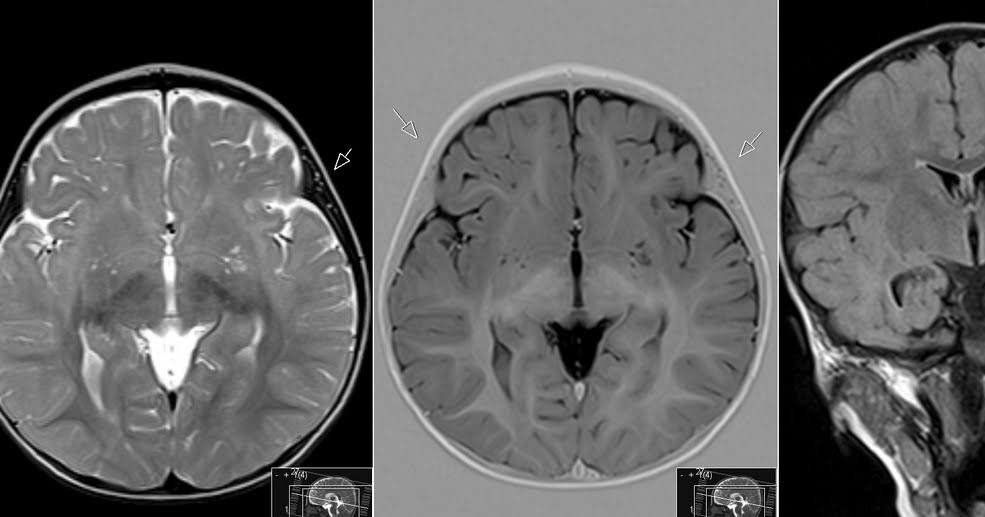

In humans, perivascular spaces surround arteries and veins can usually be seen as areas of dilatation on MRI images. While many normal brains will show a few dilated spaces, an increase in these spaces may correlate with the incidence of several neurodegenerative diseases, making the spaces a topic of research.

Perivascular spaces may be enlarged to a diameter of five millimeters in healthy humans and do not imply disease. When enlarged, they can disrupt the function of the brain regions into which they project. Dilation can occur on one or both sides of the brain.

Perivascular spaces are most commonly located in the basal ganglia and white matter of the cerebrum, and along the optic tract. The ideal method used to visualize perivascular spaces is T2-weighted MRI. The MR images of other neurological disorders can be similar to those of the dilated spaces. These disorders are:

Perivascular spaces are distinguished on an MRI by several key features. The spaces appear as distinct round or oval entities with a signal intensity visually equivalent to that of cerebrospinal fluid in the subarachnoid space. In addition, a perivascular space has no mass effect and is located along the blood vessel around which it forms.